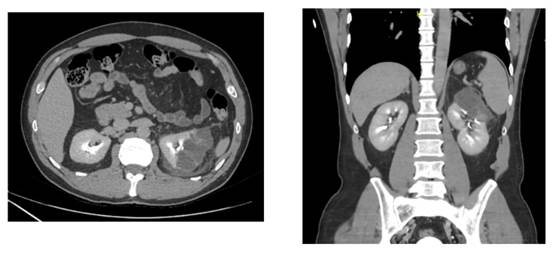

Case 5

A 19-years-old female with no medical history, presented to the ER with abdominal contusion and pain after falling from an e-scooter while riding it at 30km/h under alcohol influence. Physical exam showed many bruises, low consciousness, a bigger bruise in the right flank and significant pain with the palpation on an unstable patient. The CT scan showed liver lacerations and a shattered right kidney (Figure 11, 12 & 13) that ended with an urgent nephrectomy (Figure 14). The patient had a postoperative recovery with no incidences and went home with a normal GFR and hemoglobin, being followed afterwards with an ambulatory CT scan and renal function monitoring.

Axial, coronal and sagittal planes. Liver lacerations and a shattered right kidney.

Figure 11, 12 & 13 Contrasted abdominopelvic CT scan